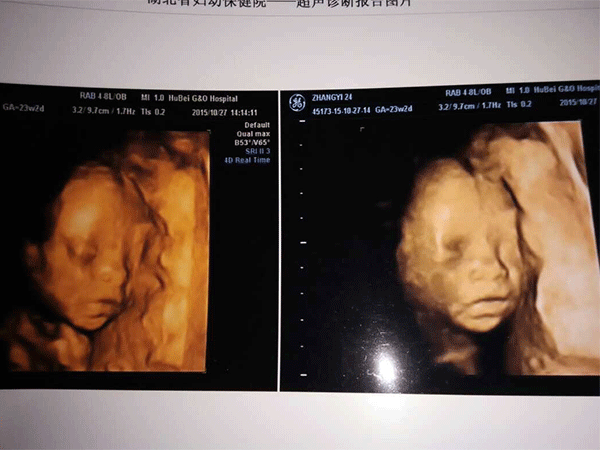

三维彩超,即彩色多普勒超声检查的一种,检查图像呈土黄色,通过多普勒超声仪器发出超声波,对体内各项器官进行成像。三维即其图像是立体的,可以更直观的看到器官的形态,及时发现病变并进行治疗。三维彩超常用于产检,用来判断胎儿的生长发育的情况或是否出现畸形等。

产检中,三维彩超通过测量子宫纵径、子宫体横径、子宫前后径这三条径线来观察胎儿是否正常。以及通过三维立体的成像,可以清晰的显示出胎儿各个内脏器官,以及面部器官、四肢的情况,来简单的判断胎儿是否存在畸形,包括胎儿是否患有先天性心脏病也是能够检查出来的。

24周的胎儿,其身体结构的生长发育已经很完善了,且胎儿大小也很合适,这时候做三维彩超可以很直观的看到胎儿的五官四肢、以及内脏器官,还能了解胎儿双顶径、头围、腹围、股骨长等发育情况。

三维和四维并不是彩色图片,只是和黑白色有差异,二者呈现的都是土黄色的画面。但三维的成像是静态的,是一张图片,而四维彩超则是动态的,像一张动图一样,并且有的医院会允许刻成光盘带回家收藏起来。